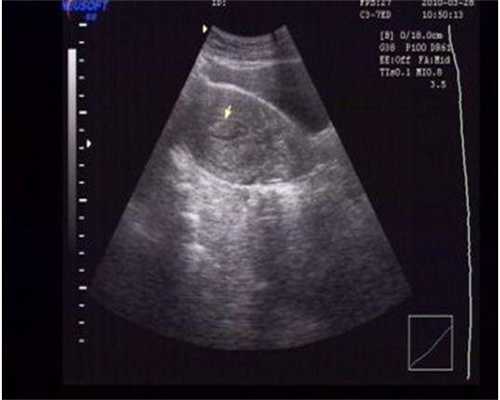

如何进行子宫子宫内膜异位症重度试管婴儿治疗?重度子宫子宫内膜异位症的试管婴儿治疗通常包括以下步骤:首先是调节月经周期和促排卵:通过使用促排卵药物调节月经周期,促进卵泡发育;然后采集卵子和精子:在超声引导下清除卵泡液,采集精子;接着是体外受精和培养胚胎: 将采集到的 卵子 和 精子 在体外结合,在培养皿中培养胚胎;最后进行胚胎移植:将健康的胚胎移植到 子宫 中,等待受精结果。